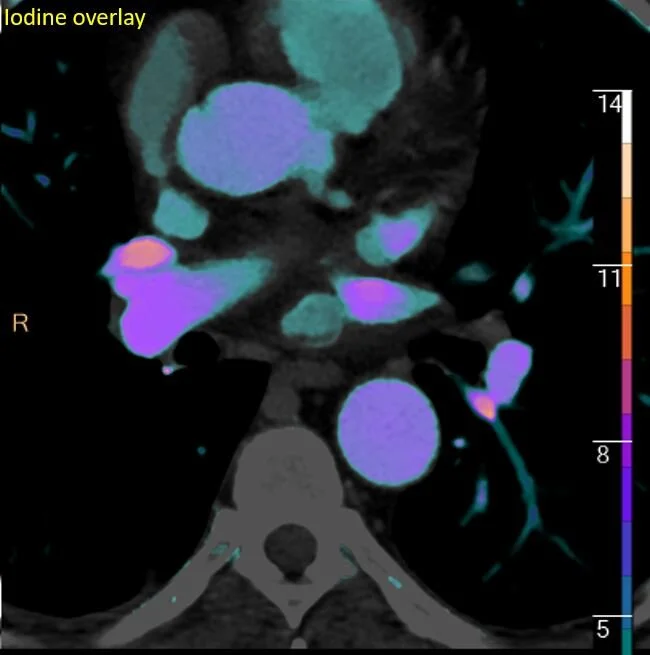

Something new for adrenal nodules